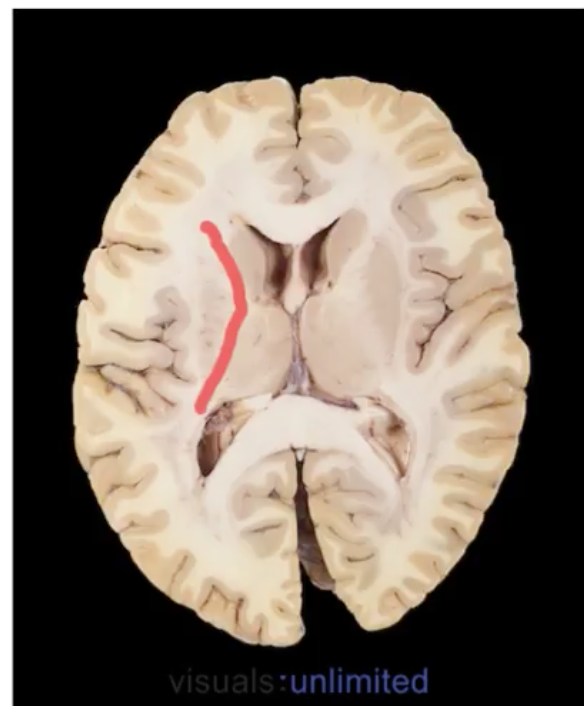

label

Caudate> C-shaped structure

appears twice

image